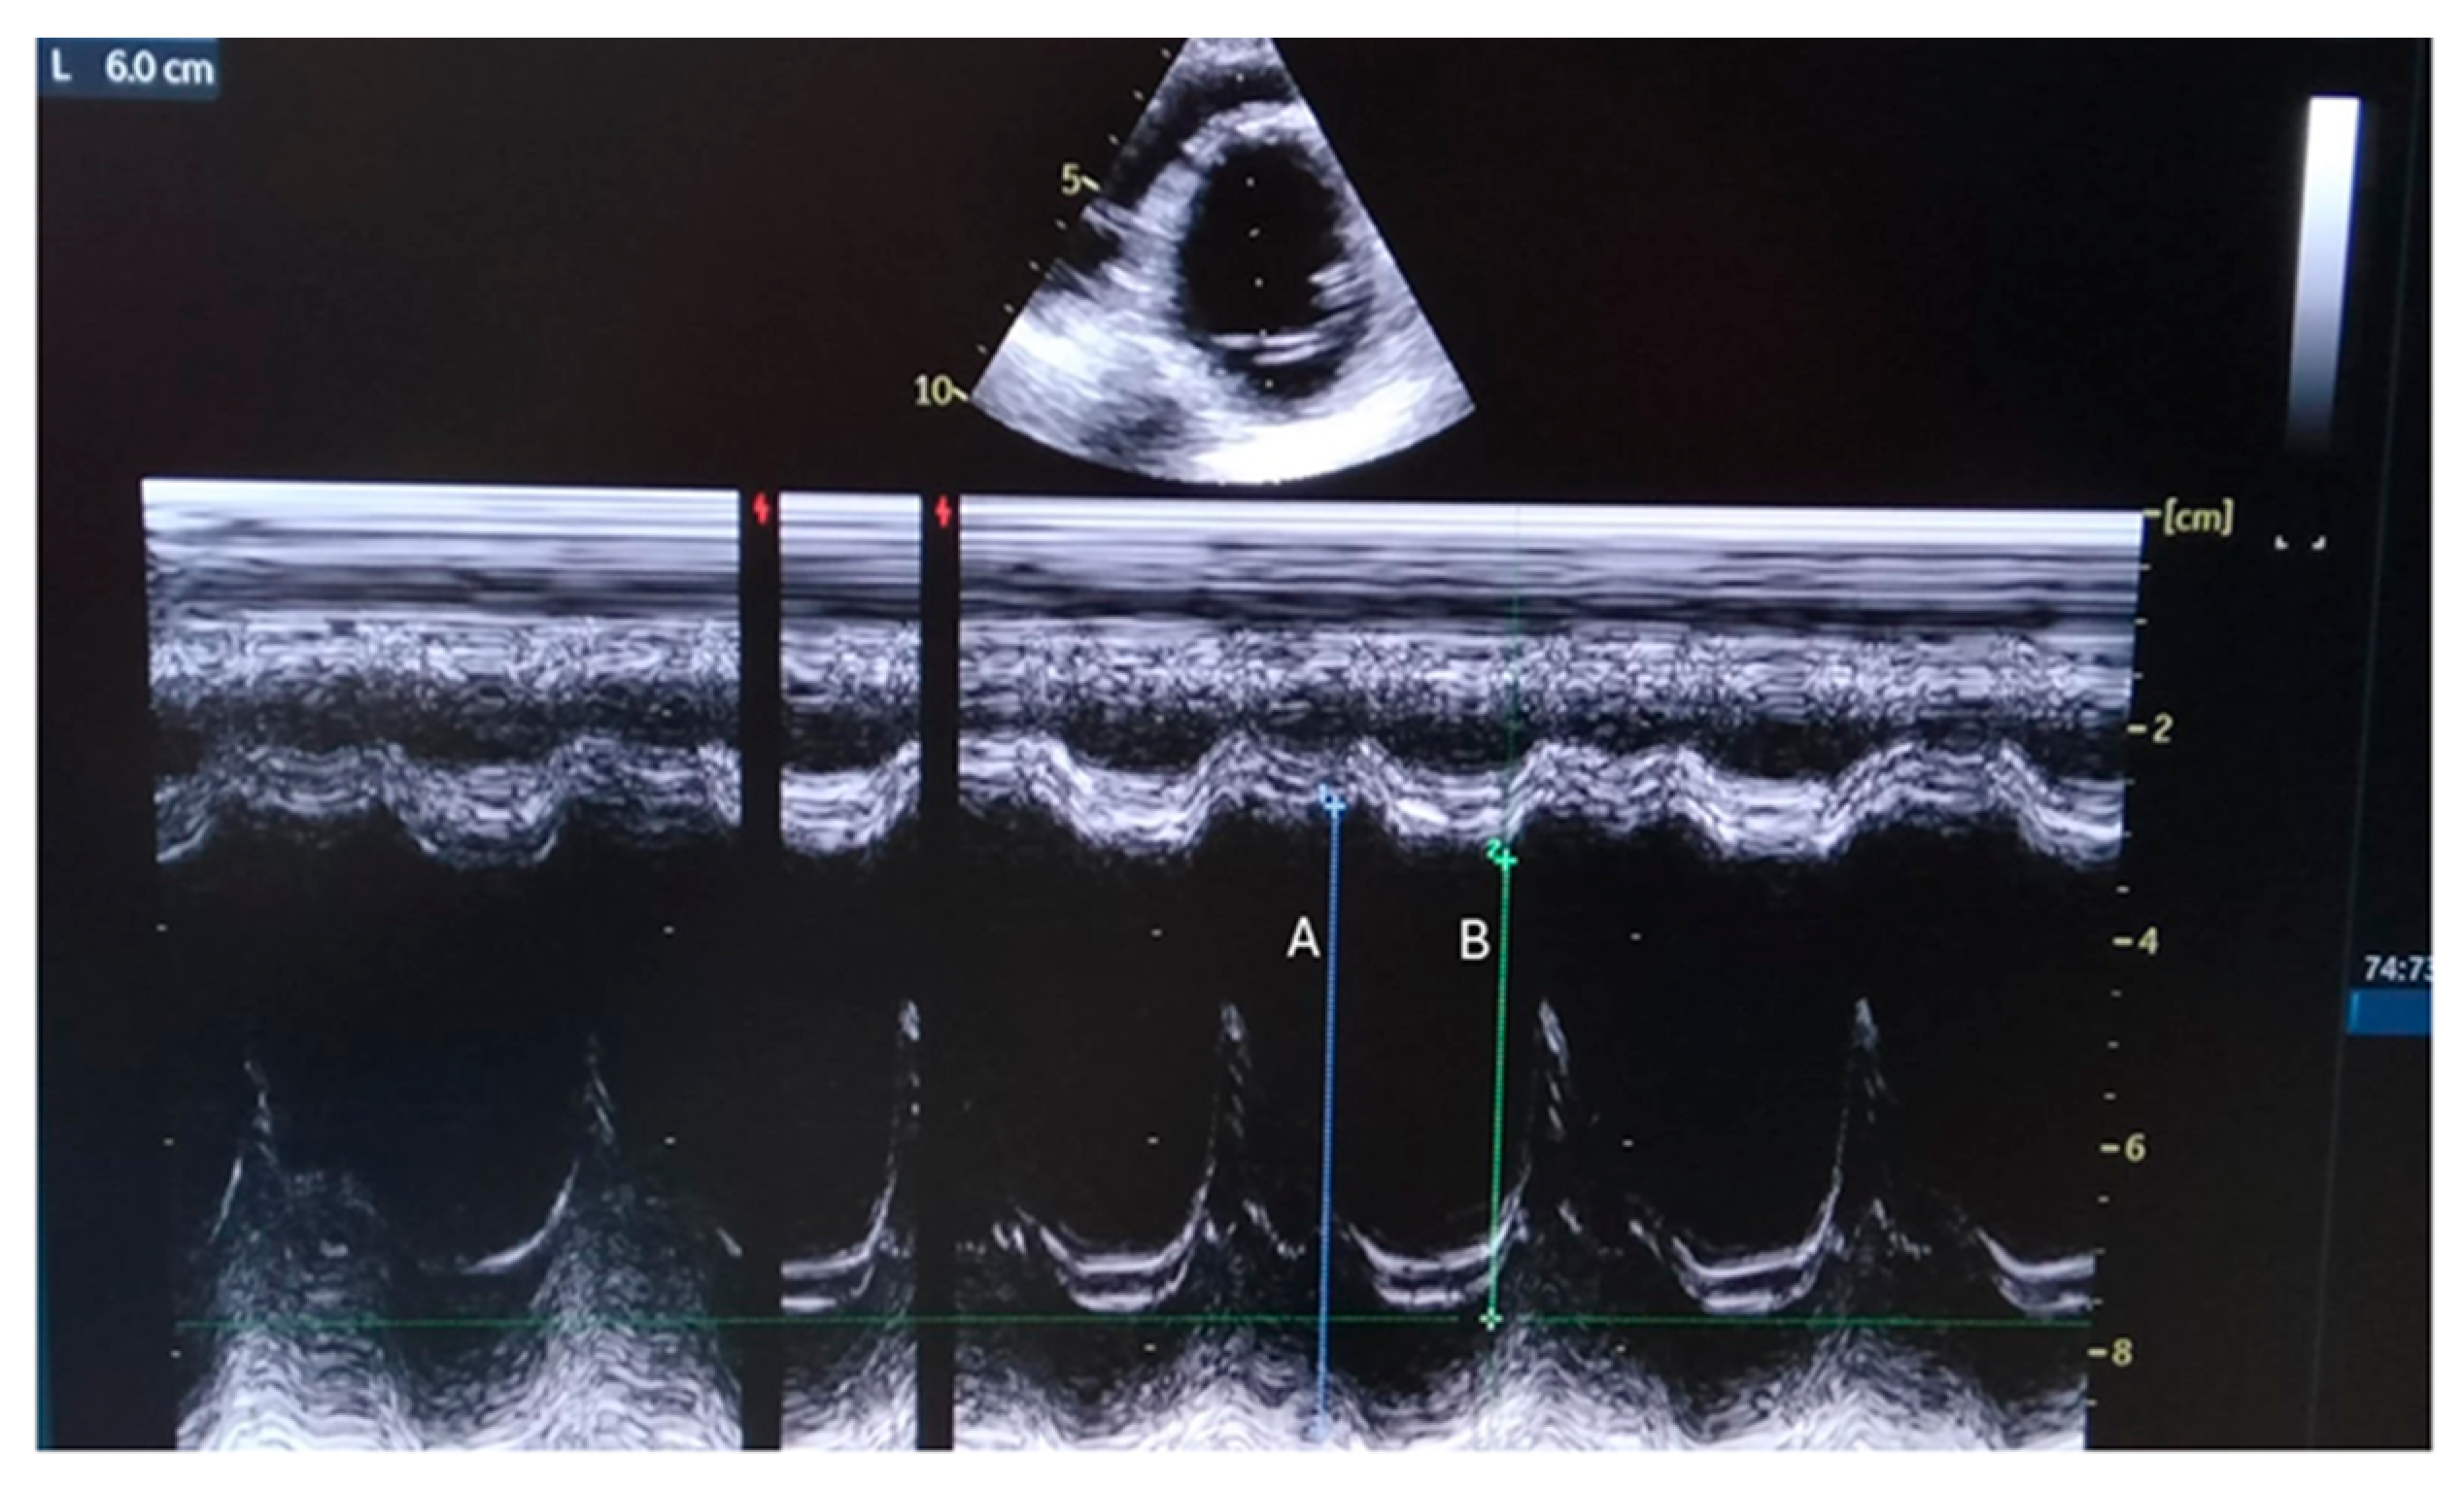

Figure 1.

Parasternal M-mode view shows internal dimensions of dilated left ventricle with reduced ejection fraction (EF about 35%). A: End Diastolic Diameter=60 mm; B: End Systolic Diameter=44 mm, Fractional Shortening = 26%).